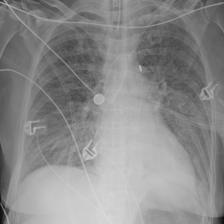

Table A.1 shows example reports generated with BioViL-T and BioViL models, which are compared to the reference radiologist’s reports. In comparison with BioViL which only models the current image, BioViL-T shows the benefit from incorporating prior study information and is able to provide factually more accurate reports especially in terms of describing temporal progression of the findings. This is showcased in the first two examples in the table: In the first row, BioViL-T is able to comment on not only the presence of the pleural effusion but also its improvement while BioViL fails to mention the change. In the second example, BioViL-T is able to correctly identify that there is no relevant change by comparing with the previous study, while BioViL wrongly hallucinates the tube in the current image as a new placement. BioViL-T can also avoid hallucination of the temporal information when there is no prior study. For instance, in the third example, BioViL-T correctly acknowledges that there is no prior image and generates the report based on information from the single current image, while BioViL hallucinates a non-exisistent prior study and wrongly generates temporal descriptions in the report.

| Reference (by radiologist) | BioViL | BioViL-T |

|---|---|---|

| No evidence of acute cardiopulmonary process. Decreased right pleural effusion. | Small right pleural effusion. | Small right pleural effusion, decreased since _. |

| No relevant change as compared to the previous image. No evidence of pneumonia or other parenchymal pathology. Normal size of the heart. No pleural effusions. | In comparison with the study of _, there has been placement of a right ij port - a - cath that extends to the lower svc. No evidence of post procedure pneumothorax. The cardiac silhouette is within normal limits and there is no vascular congestion or pleural effusion. There is some asymmetry of opacification at the bases, more prominent on the left. In the appropriate clinical setting, this could possibly represent a developing consolidation. | As compared to the previous radiograph, no relevant change is seen. The lung volumes are normal. Normal size of the cardiac silhouette. Normal hilar and mediastinal structures. No pneumonia, no pulmonary edema, no pleural effusions. |

| No previous images. The cardiac silhouette is within normal limits and there is no evidence of vascular congestion, pleural effusion, or acute focal pneumonia. | In comparison with the study of _, there is little change and no evidence of acute cardiopulmonary disease. No pneumonia, vascular congestion, or pleural effusion. | No previous images. The cardiac silhouette is within normal limits and there is no vascular congestion, pleural effusion, or acute focal pneumonia. |